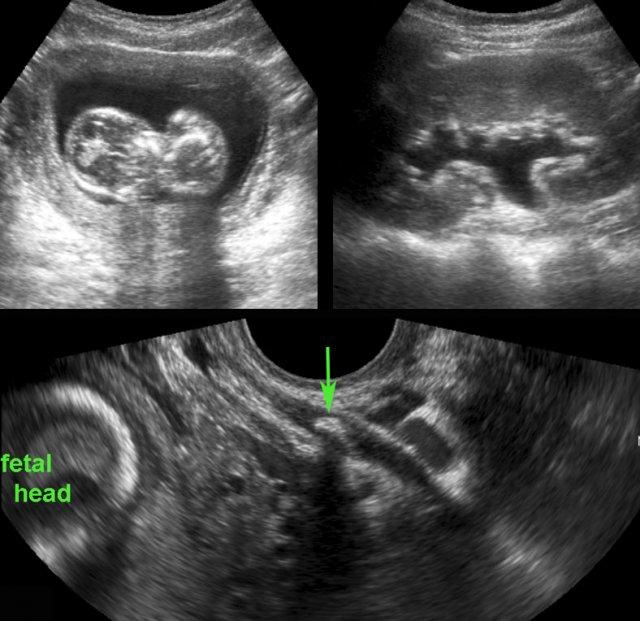

Bệnh nhân nữ trẻ, mang thai giai đoạn sớm, nhập viện vì đau vùng chậu sâu cấp tính.

Siêu âm phát hiện các hạch bạch huyết mạc treo phì đại (ln) và thai trong buồng tử cung còn nguyên vẹn.

Ruột thừa không được hiển thị. (ivc = tĩnh mạch chủ dưới, a = động mạch chậu).

TVUS dễ dàng phát hiện ruột thừa viêm đường kính 12 mm chứa sỏi phân lớn (đầu mũi tên).

Ruột thừa nằm ở vị trí trong vùng chậu và được bao quanh bởi dịch tự do.

Không có thủng tại thời điểm phẫu thuật.

Ở bệnh nhân nữ béo phì, mang thai 3 tuần này, siêu âm qua thành bụng chỉ hiển thị được ruột thừa với hình ảnh nghi ngờ bất thường (← ?).

TVUS cho thấy ruột thừa giãn to, chứa đầy mủ, đang trong tình trạng viêm, nằm ở vị trí sâu trong vùng chậu.